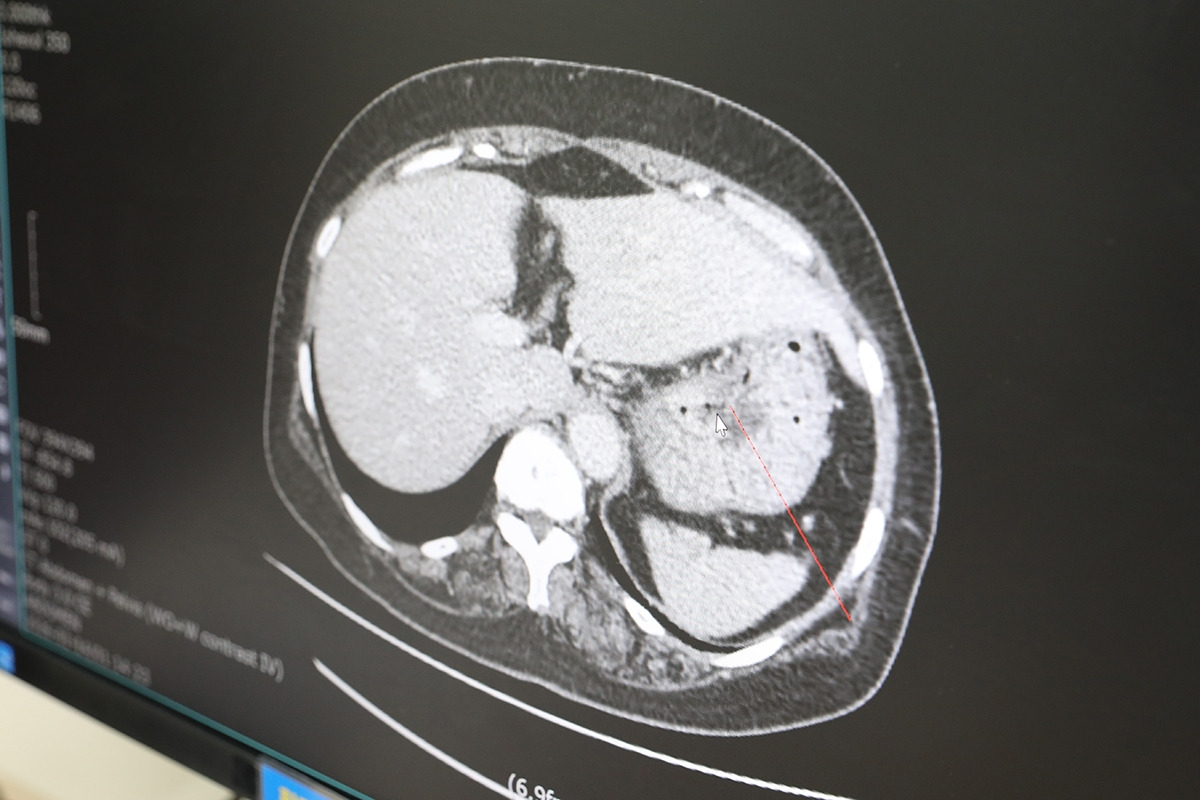

[참고자료] 위암환자 CT 사진.jpg